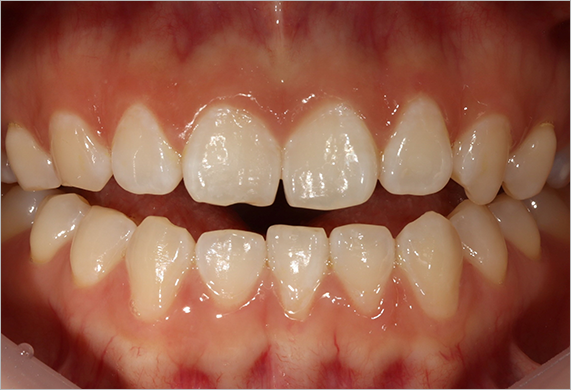

앞니 벌어짐

앞니가 마음에 안들 때 부분교정으로 해결할 수 있습니다. 부정 교합은 주로 잇몸의 공간이 부족하여 생기지만, 공간이 오히려 남아서 치아 사이가 벌어지는 경우도 있습니다. 적절한 위치를 중심으로 치아를 모아주는 치료를 해야 합니다.

앞니 벌어짐 교정 CASE

-

연세바로치과는 치료법을 준수합니다. 로그인 하시면 Before를 보실 수 있습니다. LOGIN